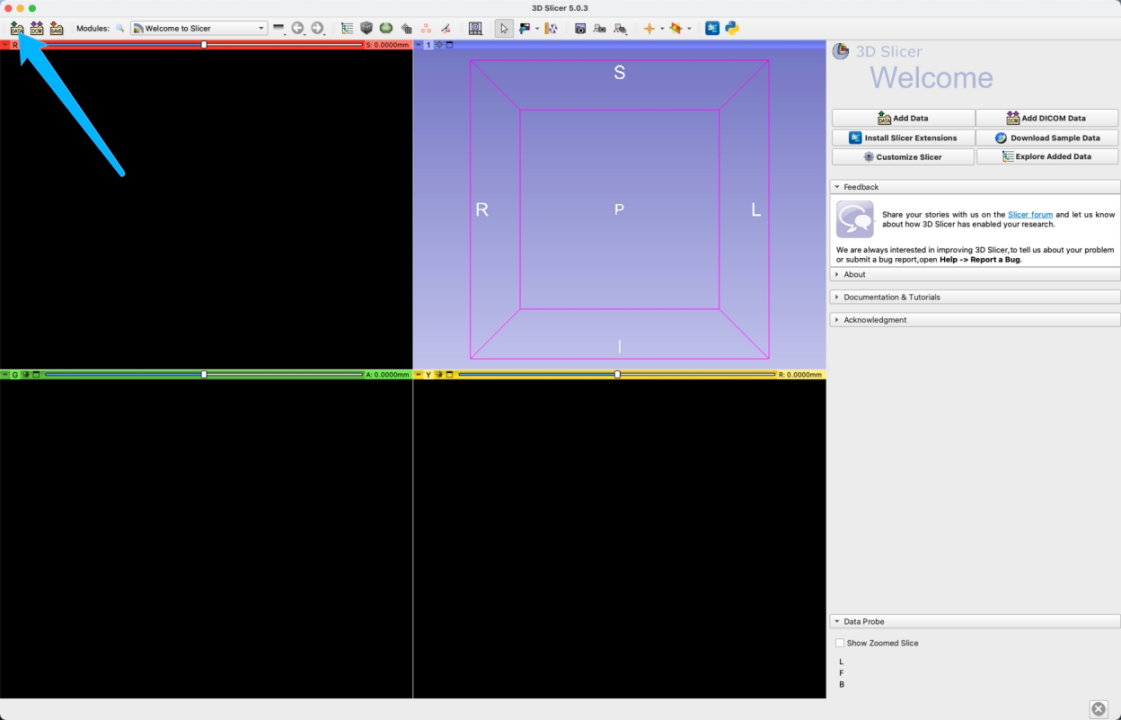

- 导入数据: